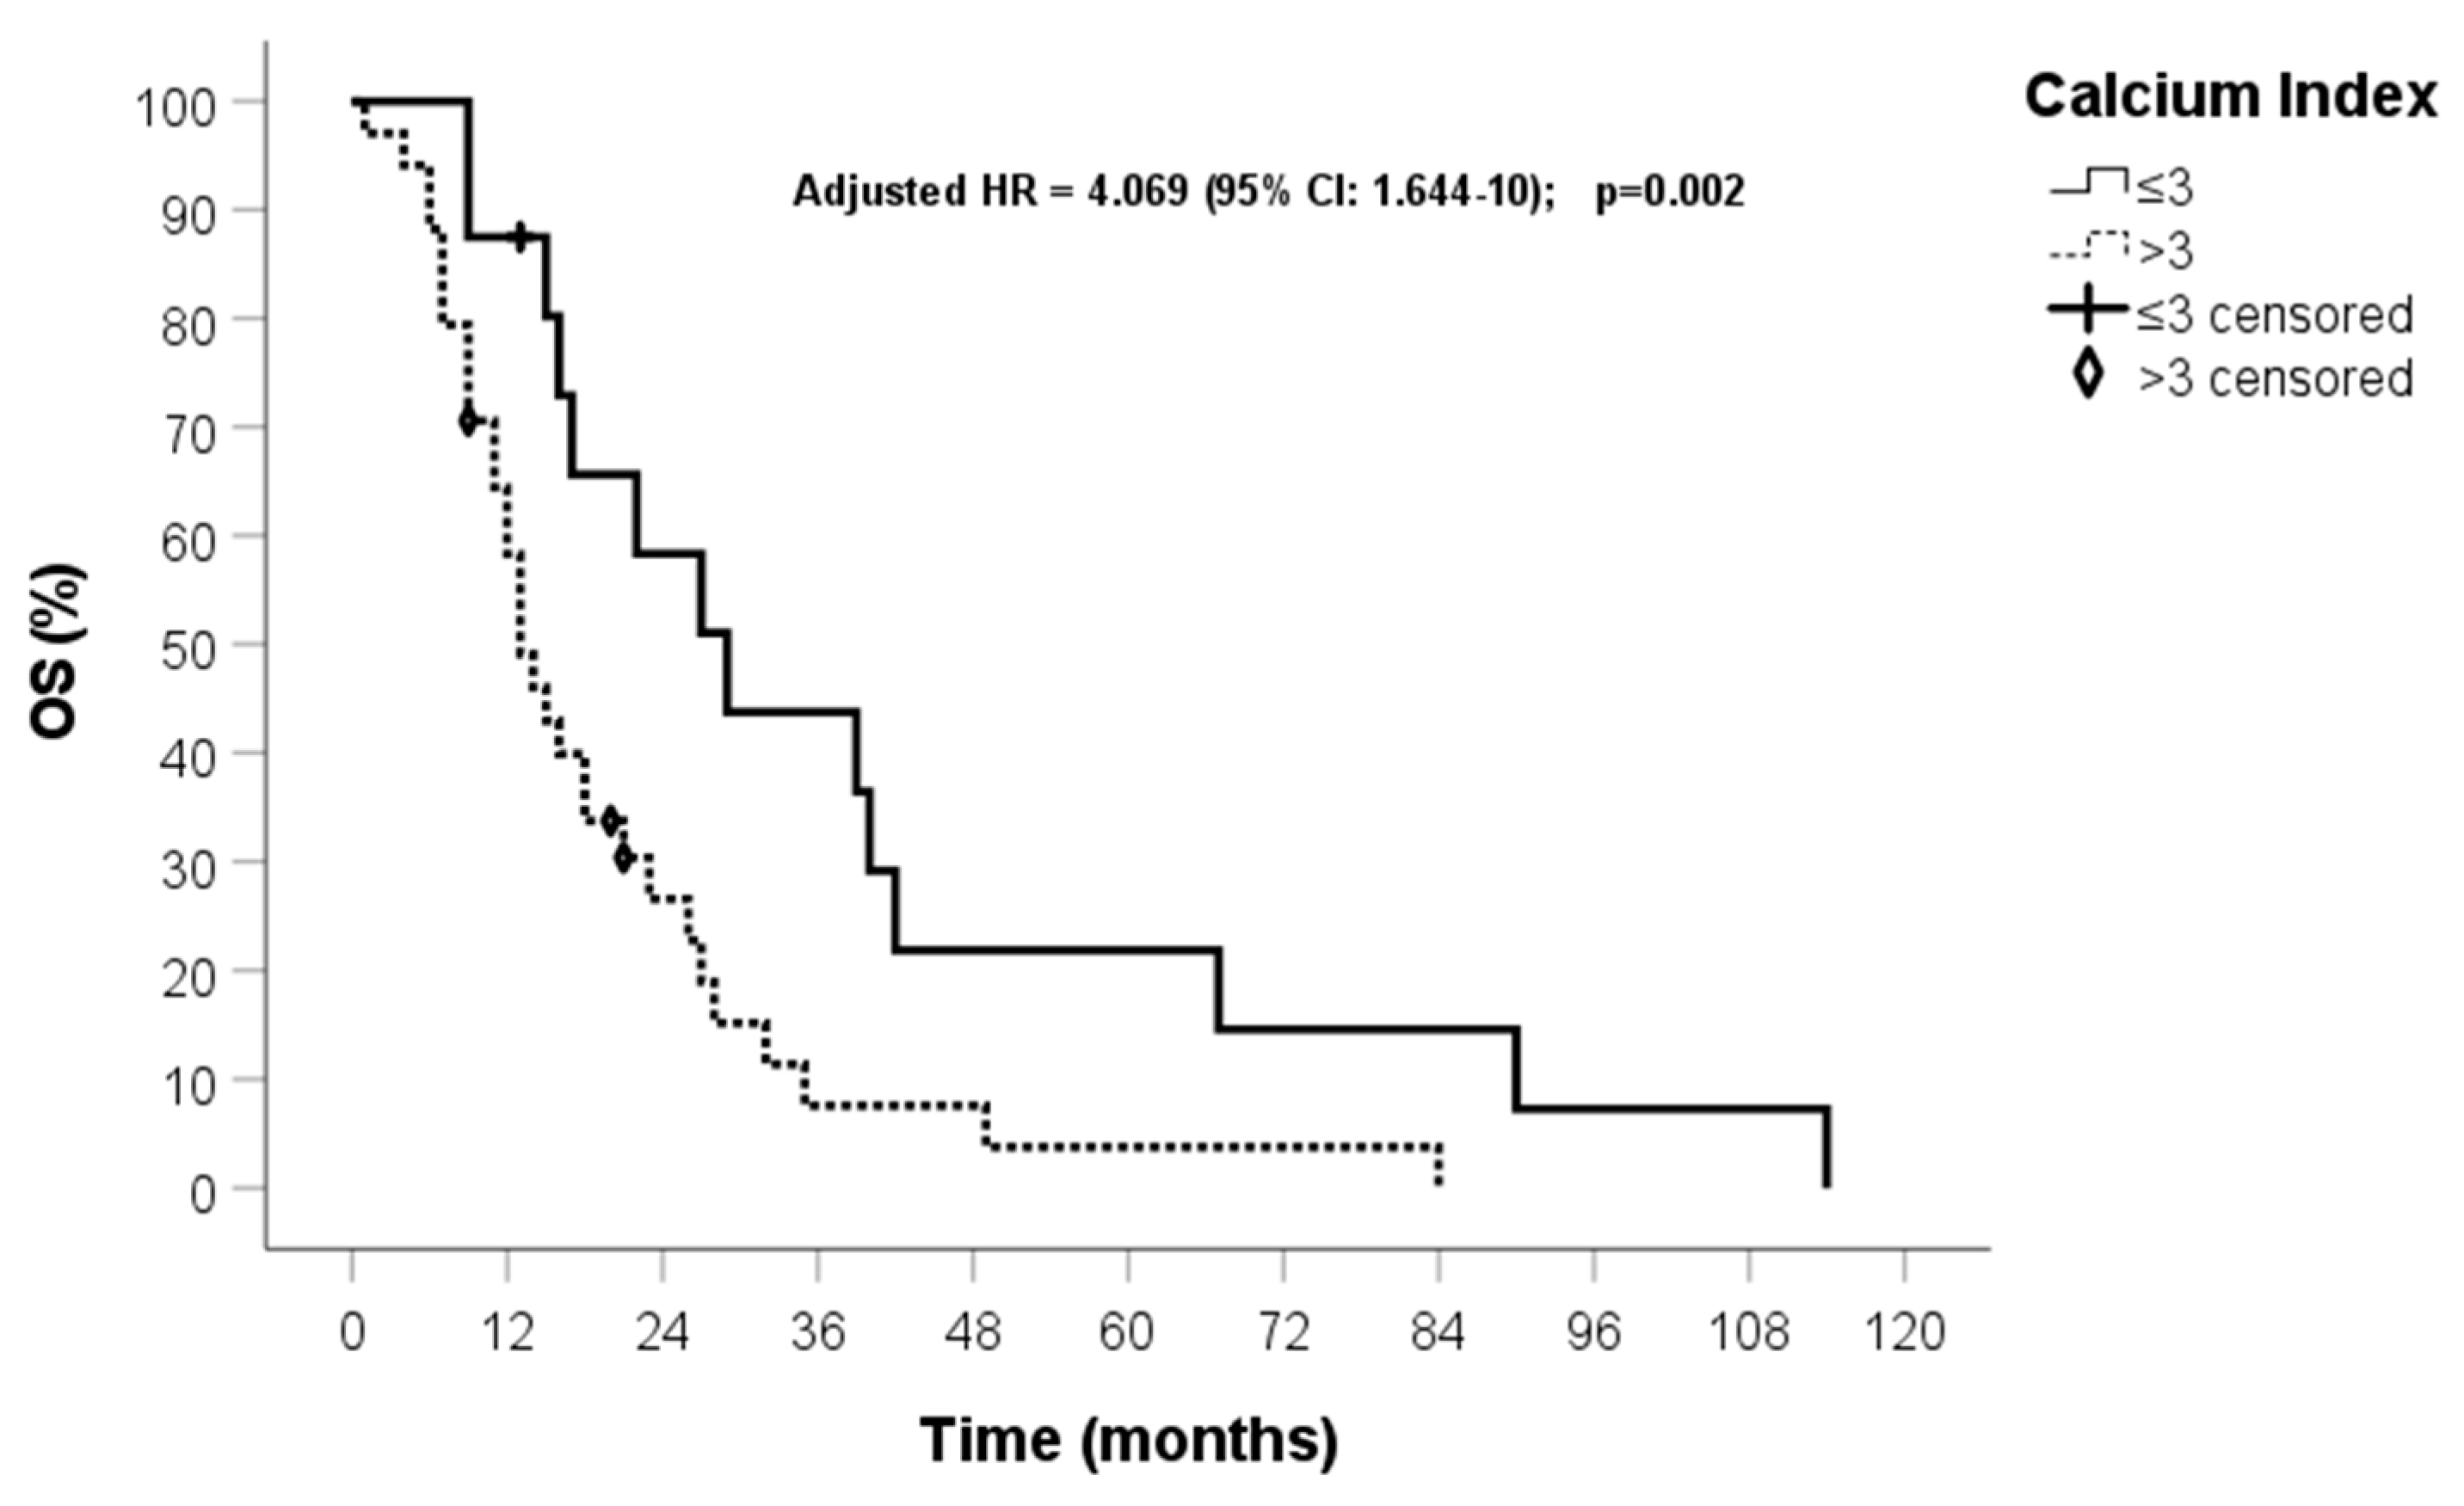

| Calcium index (0) ≤3 (1) >3 | 0.893 | 2.443 (1.229–4.855) | 0.011 | 1.912 | 6.767 (2.190–21) | 0.001 |